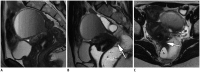

Magnetic resonance imaging is the optimal modality for pelvic imaging. It is based on T2-weighted magnetic resonance (MR) sequences allowing uterine and vaginal cavity assessment as well as rectal evaluation. Anatomical depiction of these structures may benefit from distension, and conditions either developing inside the lumen of cavities or coming from the outside may then be better delineated and localized. The need for distension, either rectal or vaginal, and the way to conduct it are matters of debate, depending on indication for which the MR examination is being conducted. In this review, we discuss advantages and potential drawbacks of this technique, based on literature and our experience, in the evaluation of various gynecological and rectal diseases.